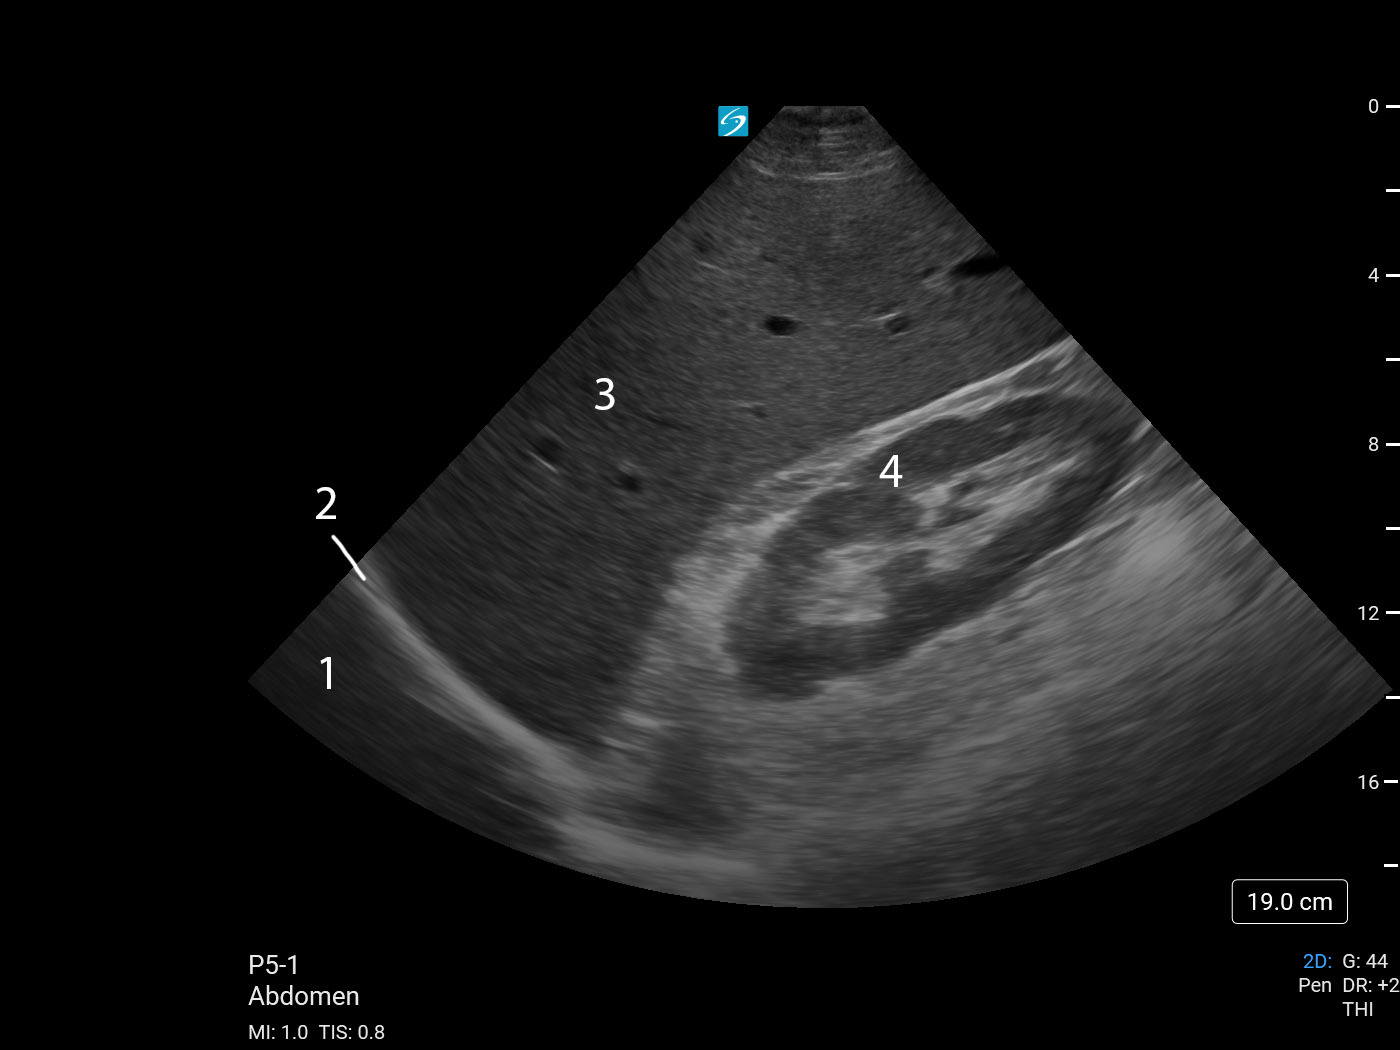

eFAST Right Upper Quadrant (RUQ) View 2 (Sonosite PX P5-1) Image

1. Pleural Space

2. Diaphragm

3. Liver

4. Right Kidney